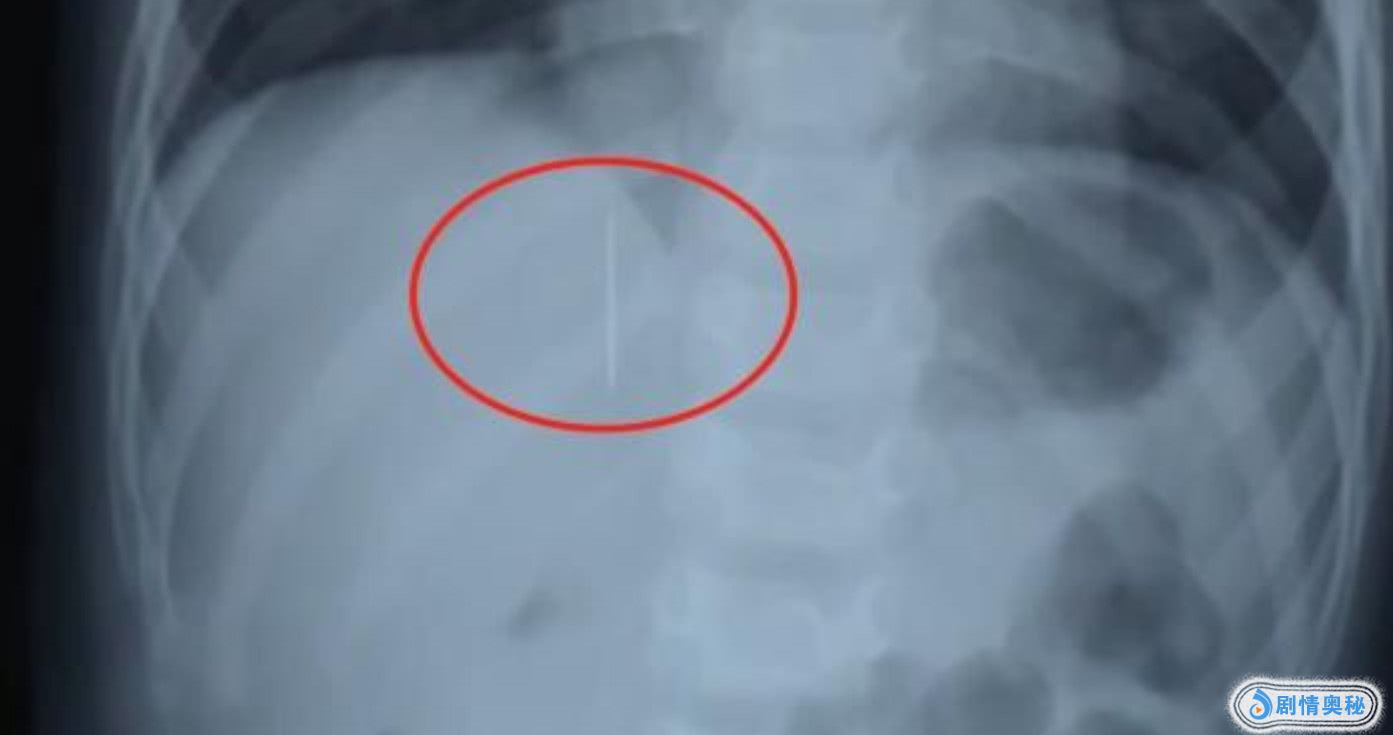

而孩子的主治医生最后也告知了记者,他们当天在检查的时候,发现孩子的肝脏部位有金属。一看,原来是根长四厘米的绣花针。医生还表示,这种情况非常危险。孩子体内扎的这跟针刚好就扎在肝脏上,稍不注意就会大出血,危及生命,医生决定立即进行手术。

医生还表示:“针在孩子体内是会游走的,要是不及时取出来,随时都有生命危险。最后,给孩子做了探查术,把针成功地取了出来,现在孩子恢复地还不错,过一段时间之后就能出院了。”现在,熙熙的状态平稳。而熙熙的父母也对此作出了回应,他们表示:应该是在给孩子缝补衣物的时候不小心把针留在衣服上了。